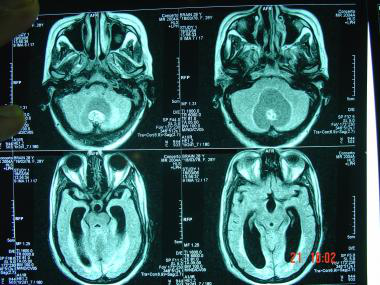

脑转移瘤是常见的医学问题。根据2008年美国癌症协会的登记,估计每年大约有140万美国人被诊断为癌症,其中近40%的患者发生一处或多处脑转移瘤...

2021-03-10 12:03:02